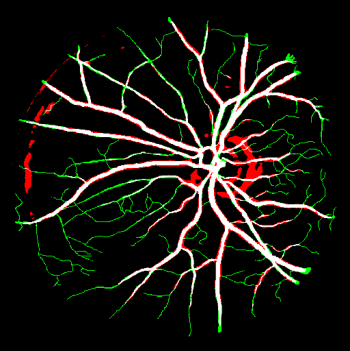

Vessel segmentation is an essential task in many clinical applications. Although supervised methods have achieved state-of-art performance, acquiring expert annotation is laborious and mostly limited for two-dimensional datasets with a small sample size. On the contrary, unsupervised methods rely on handcrafted features to detect tube-like structures such as vessels. However, those methods require complex pipelines involving several hyper-parameters and design choices rendering the procedure sensitive, dataset-specific, and not generalizable. We propose a self-supervised method with a limited number of hyper-parameters that is generalizable across modalities. Our method uses tube-like structure properties, such as connectivity, profile consistency, and bifurcation, to introduce inductive bias into a learning algorithm. To model those properties, we generate a vector field that we refer to as a flow. Our experiments on various public datasets in 2D and 3D show that our method performs better than unsupervised methods while learning useful transferable features from unlabeled data. Unlike generic self-supervised methods, the learned features learn vessel-relevant features that are transferable for supervised approaches, which is essential when the number of annotated data is limited.